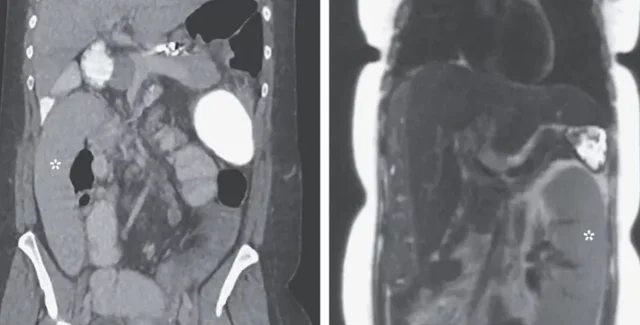

Фото: The New England Journal of Medicine

Когда 36-летняя женщина поступила в больницу Michigan Medicine в городе Энн-Арбор, врачи обнаружили ее селезенку в правом нижнем квадранте живота.

До того, как пациентка попала в больницу с "блуждающей селезенкой", она прошла обследование на рак печени, во время которого были сделаны медицинские снимки живот и селезенка была на своем месте. Через день у женщины появились боли в животе и рвота.

В отделении неотложной помощи врачи сделали новое сканирование, выяснив, что селезенка переместилась на противоположную сторону тела пациентки.

Медики предполагают, что смещение селезенки вызвала печень, которая соединяется с органом через систему вен. У женщины было диагностировано заболевание печение, называемое первичным склерозирующим холангитом. Оно характеризуется воспалением желчных протоков, по которым пищеварительный жидкости переносятся из печени в тонкий кишечник. Воспаление вызвало серьезное рубцевание печени или иными словами цирроз, который затруднил кровоток через орган.